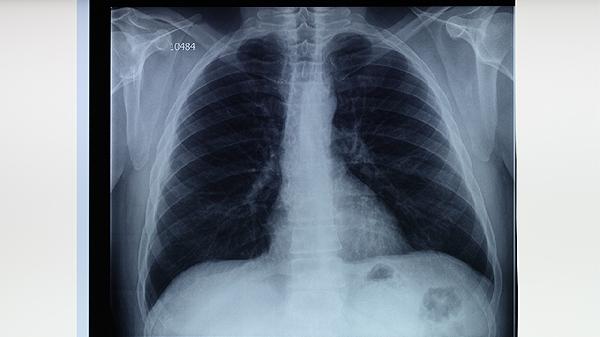

胸部X線檢查能發(fā)現(xiàn)肺結(jié)核特征性病變,如上葉尖后段或下葉背段的浸潤陰影、空洞形成等。該檢查對(duì)病變定位和范圍評(píng)估具有重要價(jià)值,但需注意與其他肺部疾病鑒別。部分早期肺結(jié)核或免疫抑制患者可能缺乏典型影像學(xué)表現(xiàn),需結(jié)合其他檢查綜合判斷。